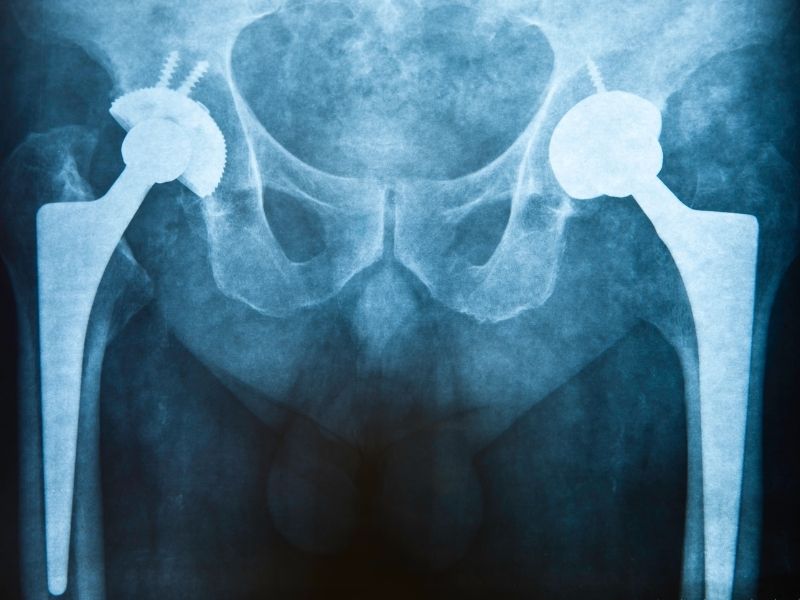

Kalça Portezi Revziyonu nedir?

Daha önce takılmış olan kalça protezinin çeşitli nedenlerle (gevşeme, enfeksiyon, şiddetli ağrı, kemik kaybı vb) çıkarılıp yerine yen protez takılması işlemidir.

Kalça protezinde gevşeme ve kırılma durumu, enfeksiyon veya protezin kullanım ömrünün bitmesi gibi nedenler kalça protezi revizyon ameliyatına neden olur.